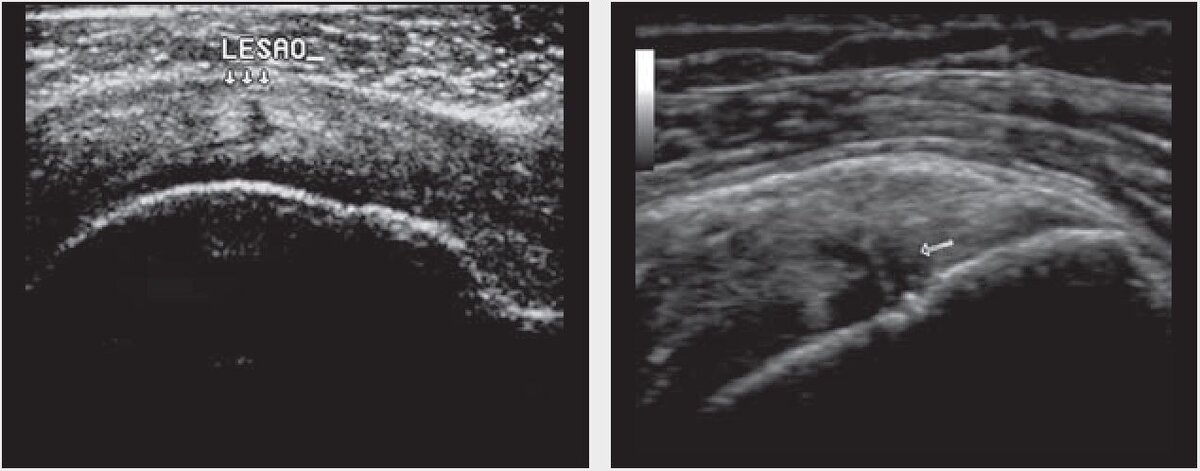

Частичные разрывы могут иметь две различные ультрасонографические картины (рис. 1). Эхонеплотные или безэховые повреждения, вызванные разрывом волокон, сначала выглядят линейно с расслаиванием сухожилия, особенно если механизм травмы является вторичным по отношению к эксцентрическому сокращению сухожилий вращательной манжеты. Чаще наблюдается смешанное поражение с эхо-богатым центром, окруженным эхо-бедным ореолом, указывающим на периплевральную жидкость. Центр с повышенной эхогенностью обусловлен втянутыми волокнами сухожилия или новым акустическим интерфейсом, образовавшимся в результате разрыва. Хотя эти формы преобладают, они не являются единственными.

Рис. 1. Наиболее распространенные ультрасонографические аспекты частичных повреждений вращательной манжеты. (a) Безэховое повреждение (стрелки), расслаивающее сухожилие. (b) Перелом смешанного типа, с эхо-насыщенными и эхо-неплотными участками внутри (стрелка).